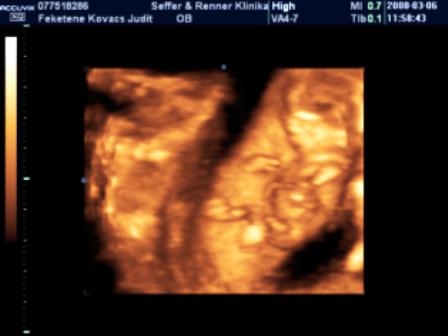

Mi holnap este megyünk.Ilyenkor még végigjárjuk a nagyszülőket + egy kis vásárolgatás, este 9-től hamarabb nem hiszem, hogy hazaérünk, de jövök majd a beszámolóval és a fotóval.